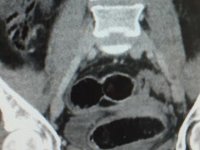

İstanbul'da uyuşturucu operasyonuİstanbul'un Pendik ilçesinde uyuşturucu satıcılarına yönelik operasyon başlatıldı.29 Haziran 2021 Salı 07:13KORONAVİRÜS  Yabancı uyruklu kadının midesinden 7 paket uyuşturucu çıktıMuş'ta polisin istihabari bilgiler üzerine takibe aldığı Rus uyruklu kadın N.O.'nun midesinden 7 paket eroin çıktı.20 Ağustos 2018 Pazartesi 09:43BASIN HABERLERİ

Yabancı uyruklu kadının midesinden 7 paket uyuşturucu çıktıMuş'ta polisin istihabari bilgiler üzerine takibe aldığı Rus uyruklu kadın N.O.'nun midesinden 7 paket eroin çıktı.20 Ağustos 2018 Pazartesi 09:43BASIN HABERLERİ  Midelerinden uyuşturucu çıktıİzmir'de iki İran uyruklu şüphelinin midesinde plastik filme sarılı 116 parça halinde toplam 810 gram metamfetamin tespit edildi, zanlılar tutuklandı08 Mart 2018 Perşembe 15:40BASIN HABERLERİ

Midelerinden uyuşturucu çıktıİzmir'de iki İran uyruklu şüphelinin midesinde plastik filme sarılı 116 parça halinde toplam 810 gram metamfetamin tespit edildi, zanlılar tutuklandı08 Mart 2018 Perşembe 15:40BASIN HABERLERİ  Tedavi gördüğü hastanede uyuşturucu satarken yakalandıTrabzon'da vücudundaki kırıklar nedeniyle hastanede tedavi gören kişide 77 adet uyuşturcu hap ele geçirildi09 Mayıs 2017 Salı 12:49BASIN HABERLERİ